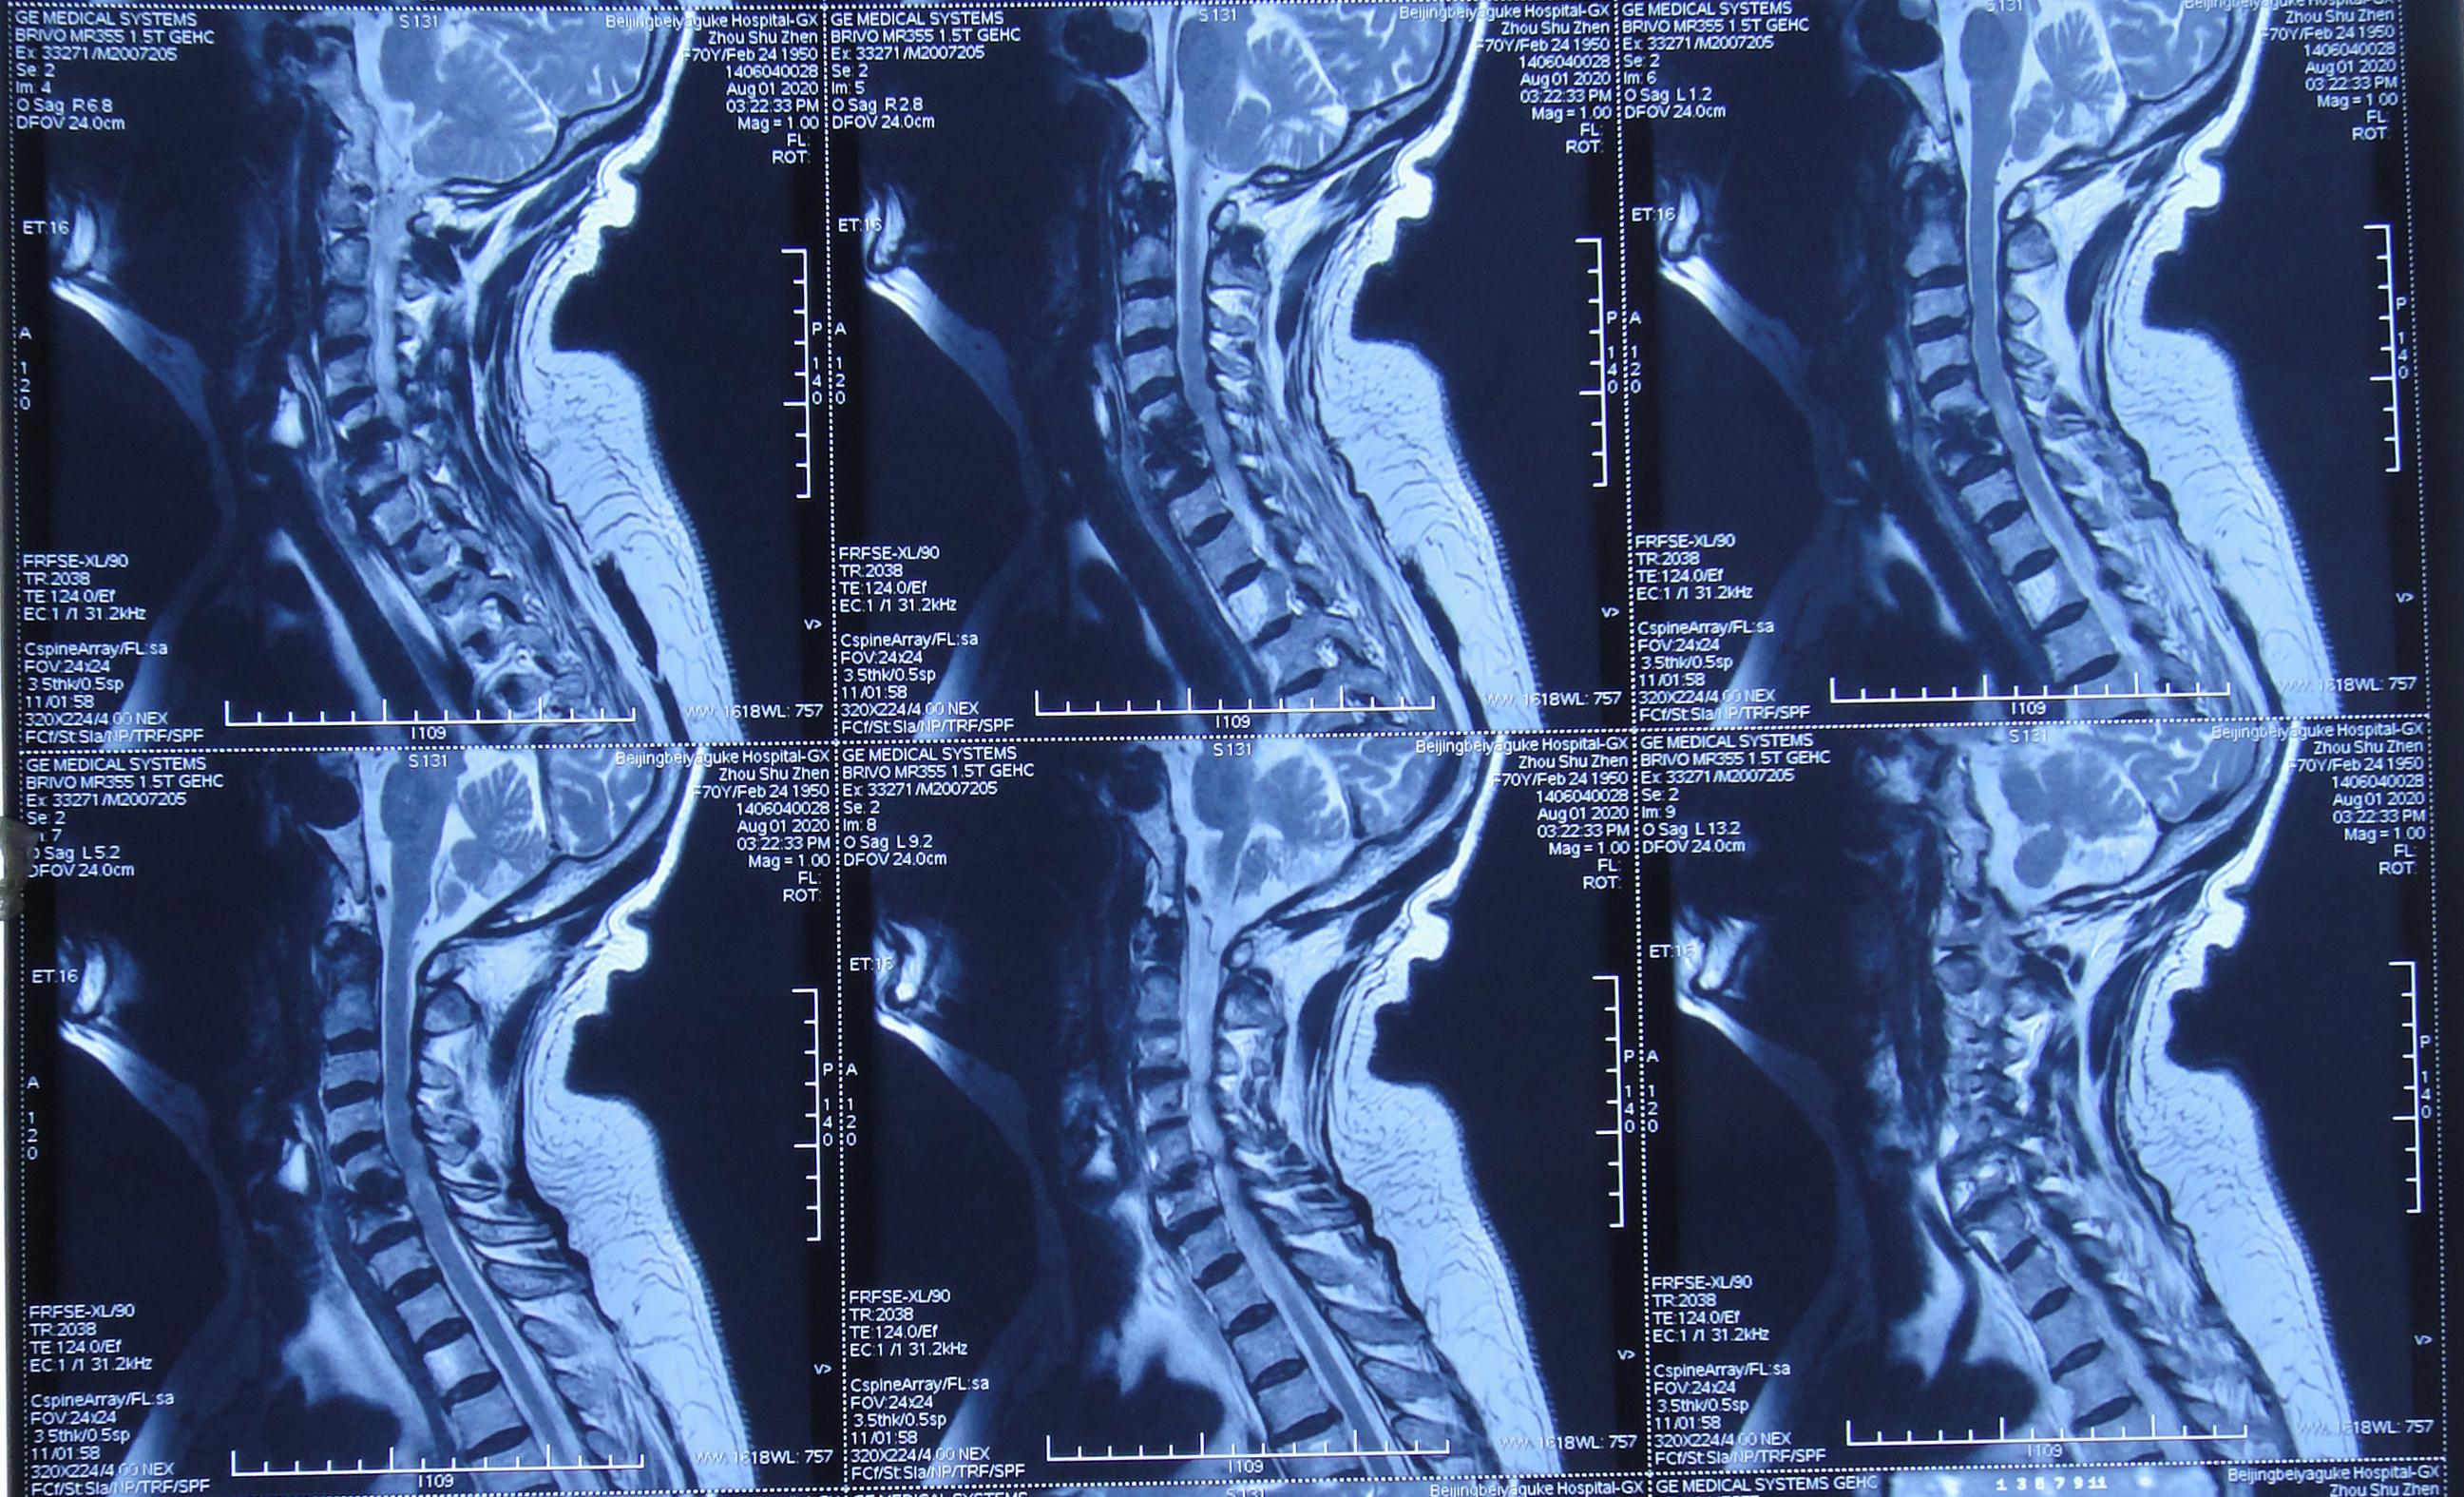

患者因间断性头晕、行走不稳,伴双上肢放射痛,麻木,于2020年4月11日入住北京某三级医院的中医骨伤科,当日查颈椎CT示椎管狭窄性颈椎病(图-1)。

图-1: 2020年4月11日颈椎CT

入院后第二天2020年4月12日查颈椎MR示颈椎病(脊髓型)( 图-2 )。

图-2: 2020年4月12日颈椎MR